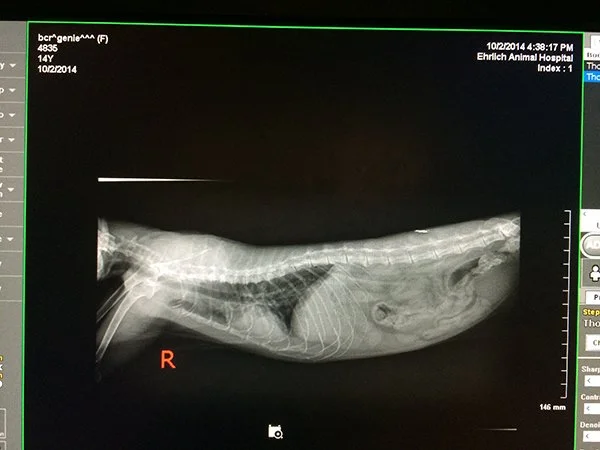

Vet-Genie-Sandcat X-rays

No spinal issues and her lungs don’t look terrible, but she has a case of bronchitis.

This is good news, because Genie Sandcat is given a long lasting antibiotic shot and has a good chance at recovery.